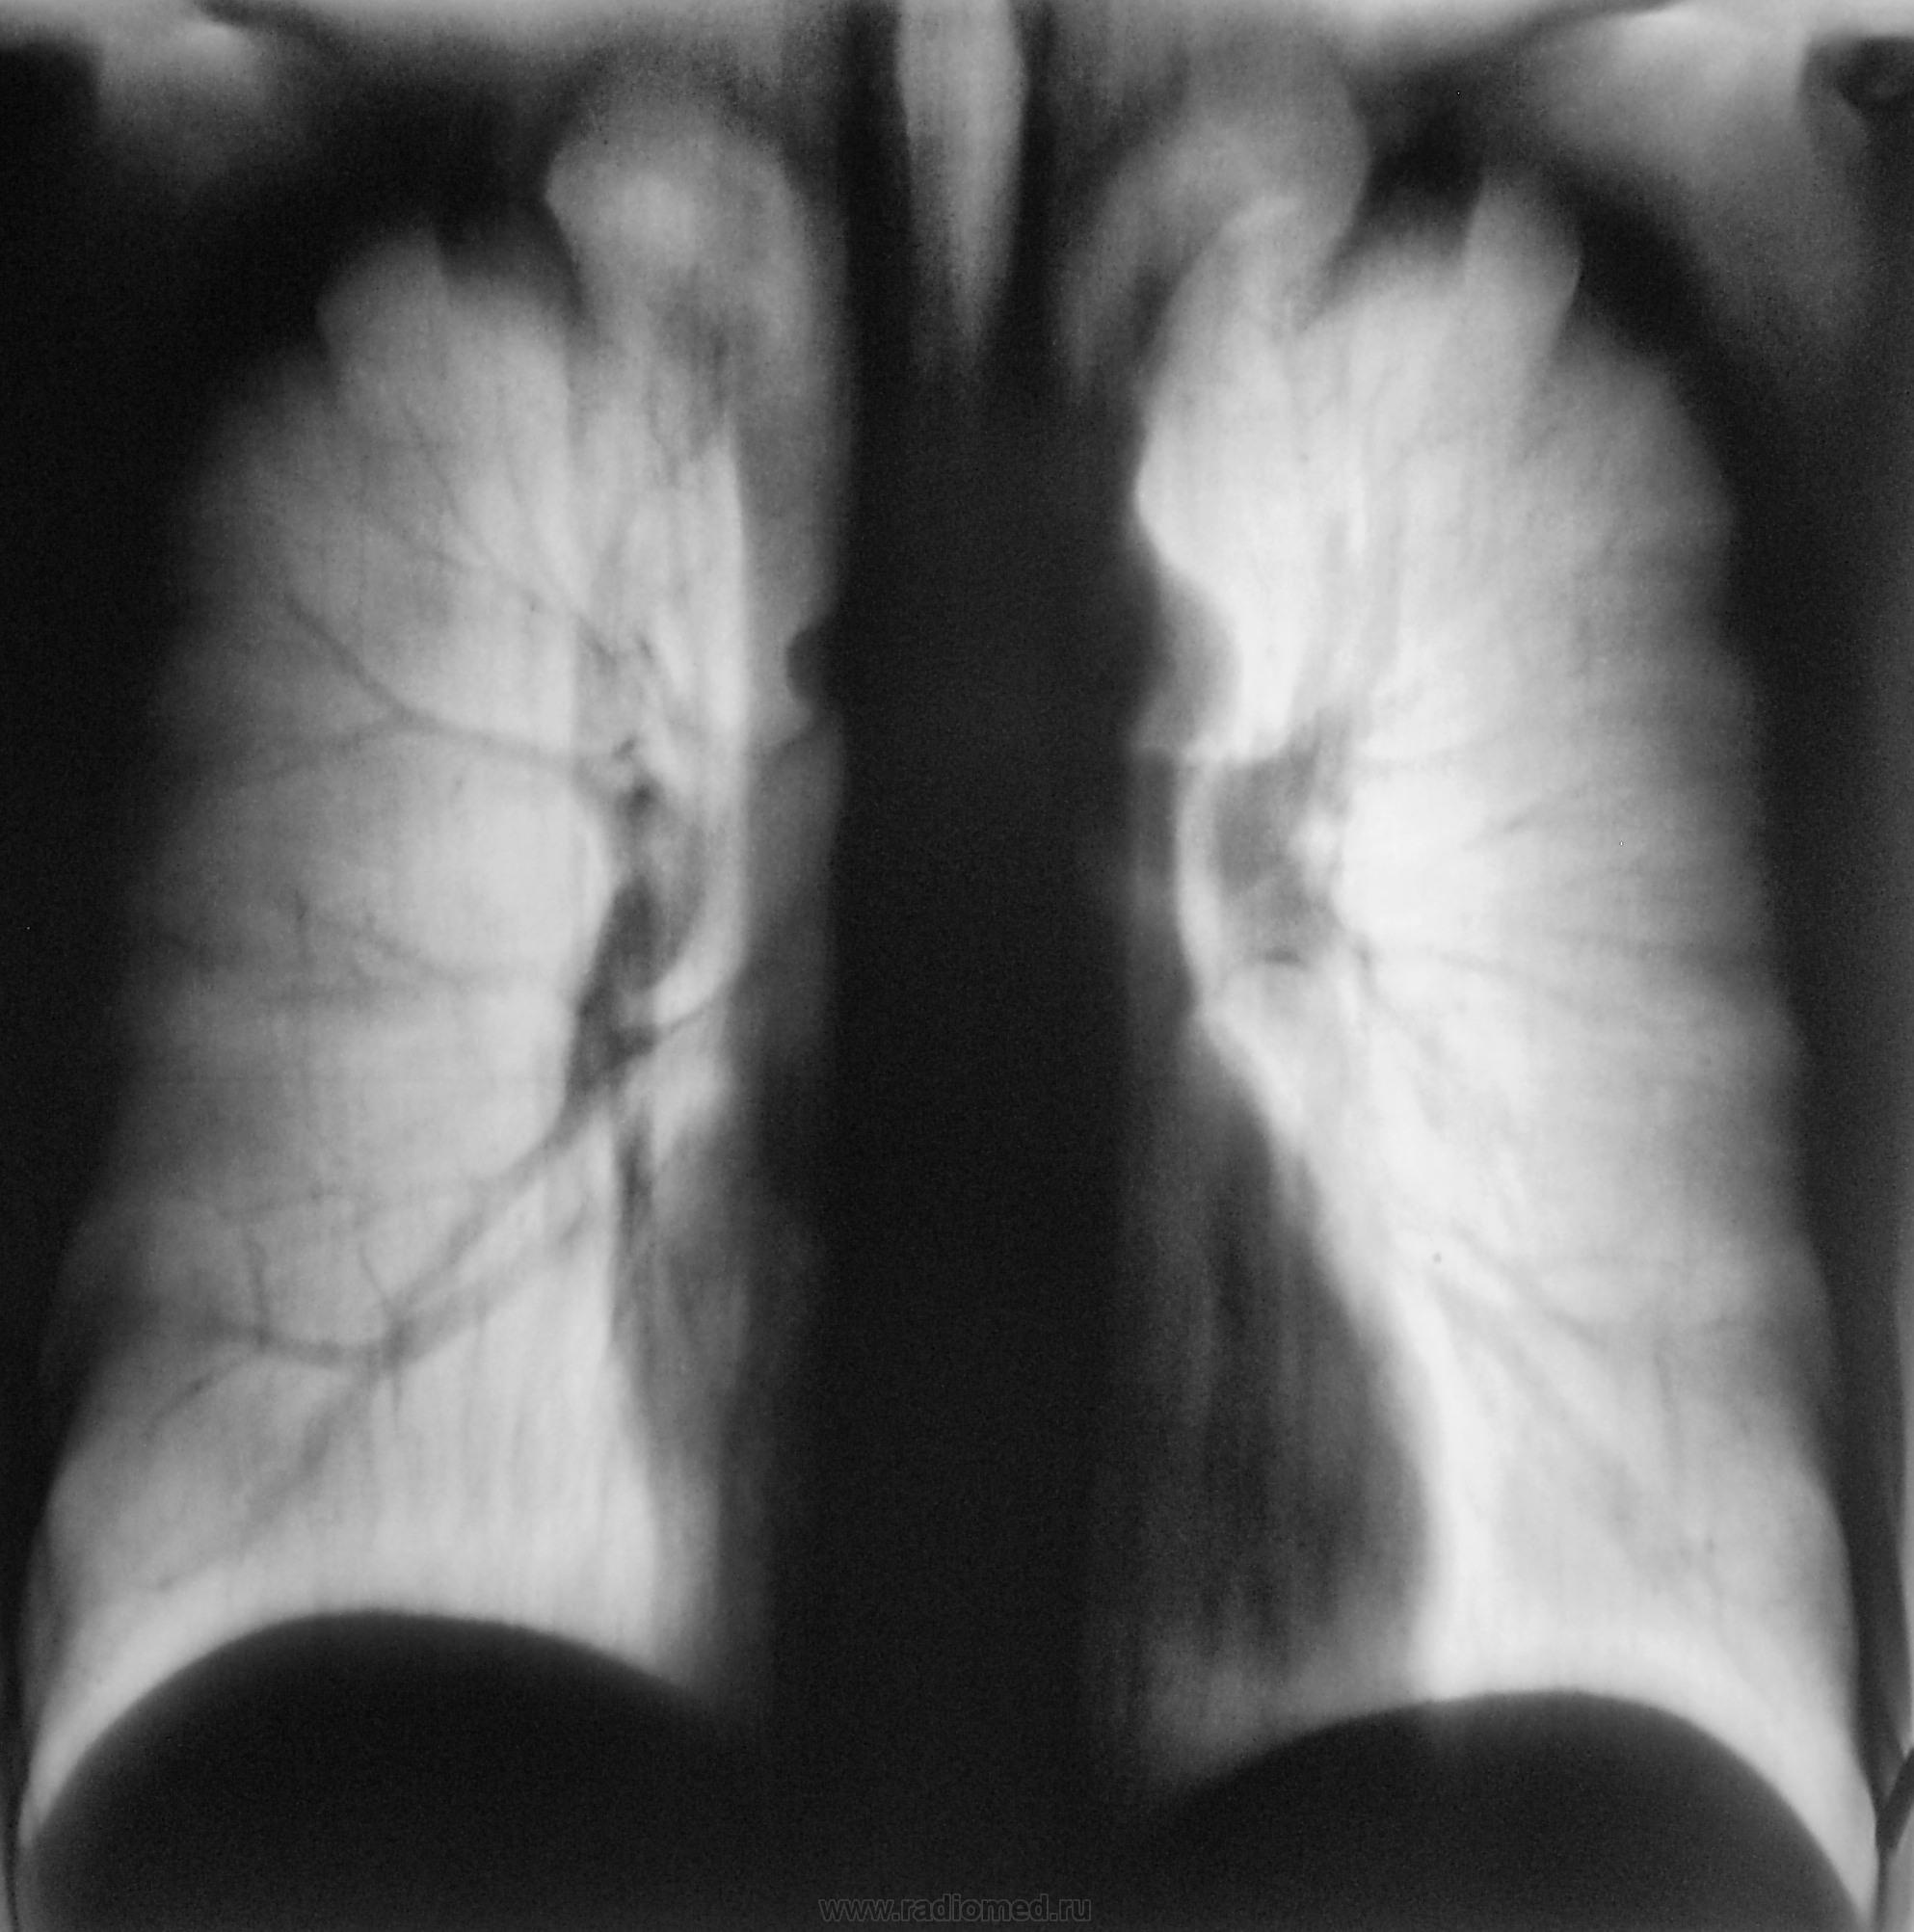

Да, у меня, как правило, "танец" начинается с верхушек.

И, интересует мнение коллег, хотя бы по этому одному срезу.

Смотрите рисунок.  Заключение написано на снимке. Кроме очагов в легких, имеется увеличение паратрахеального лимфатического узла. В ПТД на лечение.  Nikolas

Но самое интересное то, что выставленные иллюстрации - это "вторая часть" (менее интересная), так называемого "Марлизонского балета". Первую часть сейчас выставлю.

Дело в том, что этого пациента я зацепил еще год тому назад.

Снимки ниже.